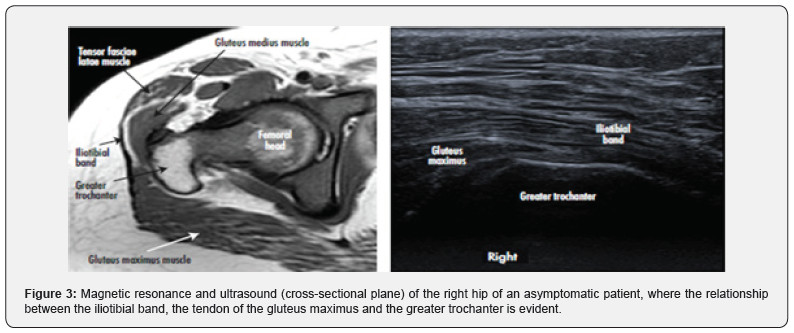

Hyperintense greater trochanteric bursal inflammation or a fluid collection may also be visualized on T2; however, these findings are non-specific and the correlation with the clinical examination is important. Post-contrast imaging can show peritendinous enhancement of involved structures. A small case series correlated atrophy of the gluteus maximus muscle on MRI with external snapping hip. The authors hypothesized that this finding could be due to gait changes to avoid pain. Finally, MRI is also useful to exclude other extra or intra-articular hip abnormalities [29]. Ultrasound has become one of the most commonly used tools for snapping hip. Ultrasound can detect bursitis, tendinitis, and synovitis [5] Dynamic ultrasound can detect abrupt movement of the involved tendon (Figure 3) [30- 33]. With external snapping hip, abrupt anterior movement of the ITB or gluteus maximus may occur as the hip is moved from extension to flexion or flexion to extension [34-35].

The linear transducer (9-12 MHz) is placed transversely over the greater trochanter, and the patient is asked to flex and externally rotate the hip: the abrupt snapping tendon during hip motion can be detected [5,19]. But there is still no consensus to determine diagnostic parameters [2,30].